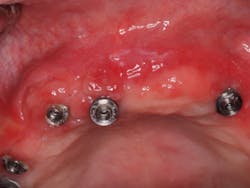

I removed the bridge to find the intaglio packed with food debris. The patient’s tissue was inflamed (figure 3), and she had developed a fungal infection. This could have been avoided with better presurgical preparation, adequate bone reduction, and proper vertical space development, which would have allowed the lab to make a hygienic intaglio (figure 4). Note the smooth and flowing intaglio surface in Figure 4. This is a bridge that can be easily maintained by the patient and hygienist.

Figure 3: Inflamed tissue from an inability to clean under the bridge